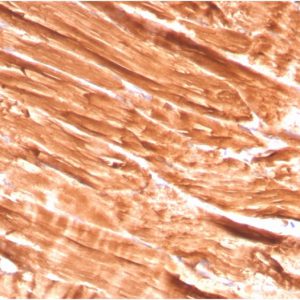

Dystrophin (DMD) (Marker of Duchenne and Becker Muscular Dystrophy) Antibody [DMD/3244]

DMD

ELISA, Immunohistochemistry

Human

Dystrophin (DMD) (Marker of Duchenne and Becker Muscular Dystrophy) Antibody [DMD/3676]

Dystrophin (DMD) (Marker of Duchenne and Becker Muscular Dystrophy) Antibody [DMD/3242]

Dystrophin (DMD) (Marker of Duchenne and Becker Muscular Dystrophy) Antibody [DMD/3245]

Dystrophin (DMD) (Marker of Duchenne and Becker Muscular Dystrophy) Antibody [DMD/3241]

Dystrophin (DMD) (Marker of Duchenne and Becker Muscular Dystrophy) Antibody [DMD/3243]

Dystrophin (DMD) (Marker of Duchenne and Becker Muscular Dystrophy) Antibody [DMD/3677]

Dystrophin (DMD) (Marker of Duchenne and Becker Muscular Dystrophy) Antibody [DMD/6270]

Immunohistochemistry

Dog, Human